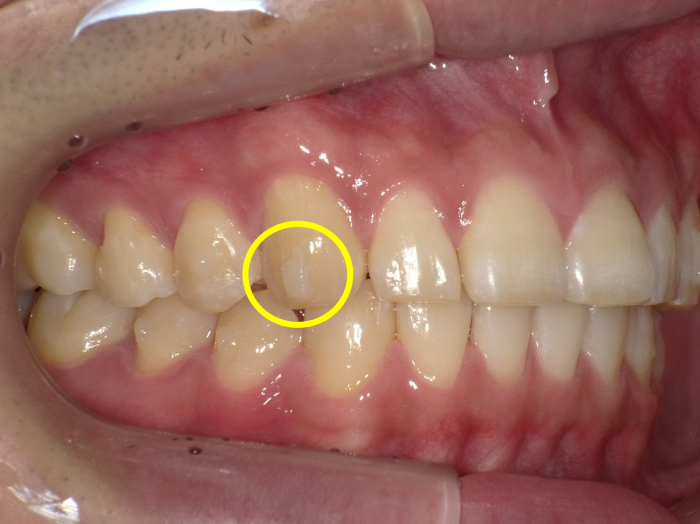

マウスピース型矯正装置(インビザライン)の治療では、アタッチメントと呼ばれる小さな突起を歯の表面に装着します。アタッチメントは、直径約1mmほどの大きさで、虫歯治療にも使用される白い歯科用レジン素材でできています。

人と人が会話をする際の距離は、最も近くても約75cmといわれています。マウスピースを装着した状態で、その距離から見た場合、ほとんどの方はアタッチメントに気づかれることはありません。

それでも、特に前歯にアタッチメントが付くことに抵抗を感じる方(とくに成人女性の方)もいらっしゃいます。そのような場合は、治療に支障のない範囲でアタッチメントの数を減らすことも可能です。

症例によっては、歯の裏側にアタッチメントを設置できる場合もあります。